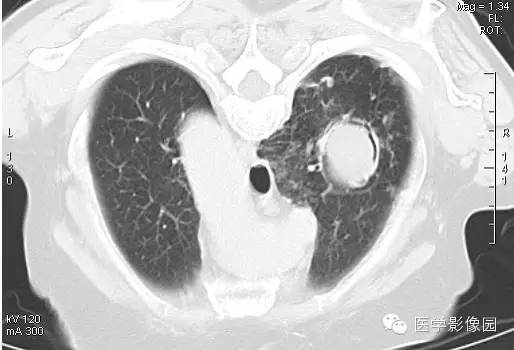

CT表现

右肺内见一圆形空洞病灶,内有圆形曲菌球,边缘光滑,可随体位改变而变动,曲菌球与洞壁之间可见“新月征”。

影像表现为肺内空洞病灶内有圆形软组织密度影,改变体位后曲菌球位置可变动,曲菌球与洞壁见出现一新月形间隙,称为“新月征”。